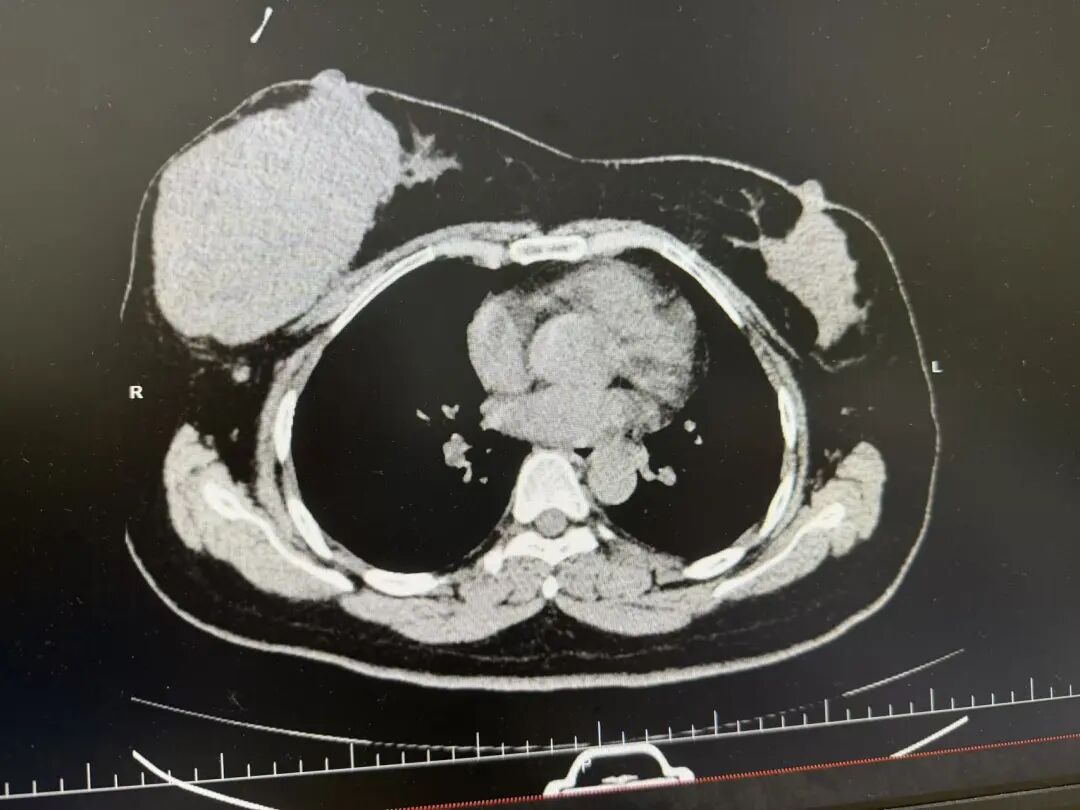

近日,岳阳市人民医院乳甲外科团队成功为38岁的白女士实施右乳巨大肿物切除+筋膜组织瓣成形术。手术不仅精准拆除了困扰患者10个月的巨大肿瘤,更通过巧妙的即刻修复技术,最大限度地保留了乳房的自然外形,实现了功能与形态的完美统一。

面对体积如此巨大的肿瘤,手术团队在术前进行了全面评估,精准规划了肿瘤切除范围与修复路径。术中,戴君副主任医师、傅智敏主任医师与李兰主治医师配合默契,在完整切除肿瘤、确保切缘阴性的同时,直面巨大组织缺损的挑战。他们创新性地利用患者自体的筋膜组织瓣,即刻、精准地修复了乳房缺损,整个手术过程出血量仅约20毫升。术后,白女士恢复迅速,次日即可下床活动,且对术后形态表示满意,实现了生理减负与心理慰藉双重愿望。

乳腺叶状肿瘤是一种较为罕见的纤维上皮性肿瘤,虽多为局限性生长,但具有易复发的特性,因此手术需要在彻底切除病灶与尽可能保留乳房外形之间取得精细平衡。本例手术的成功,体现了医院乳甲外科在复杂乳腺疾病诊疗领域,特别是在肿瘤切除后的一期修复与乳房重建技术上的深厚积累,是该科个体化治疗与人文关怀并重诊疗模式的又一次生动实践。